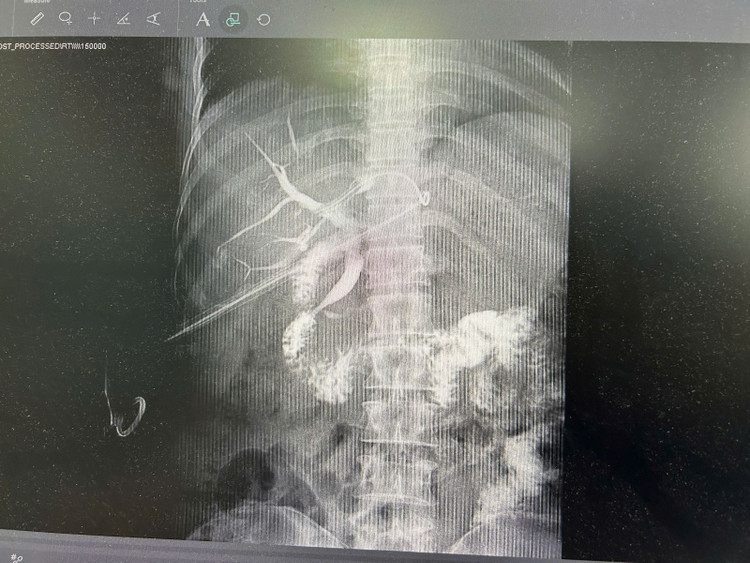

Hình ảnh ống mật đã được làm sạch sỏi sau phẫu thuật trên bệnh nhân N.T.L 45 tuổi - Ảnh BVCC

Ca phẫu thuật kéo dài khoảng 2 giờ đồng hồ, khi kết thúc người bệnh được kiểm tra lại bằng Xquang, siêu âm đường mật đảm bảo không còn sỏi sót lại.

Các vị trí phát hiện có sỏi sẽ được tán nhỏ, hút ra ngoài và bơm rửa lấy hết cặn sỏi. Kết thúc ca tán sỏi, người bệnh được kiểm tra lại bằng Xquang và siêu âm đường mật, đảm bảo không còn sót sỏi.